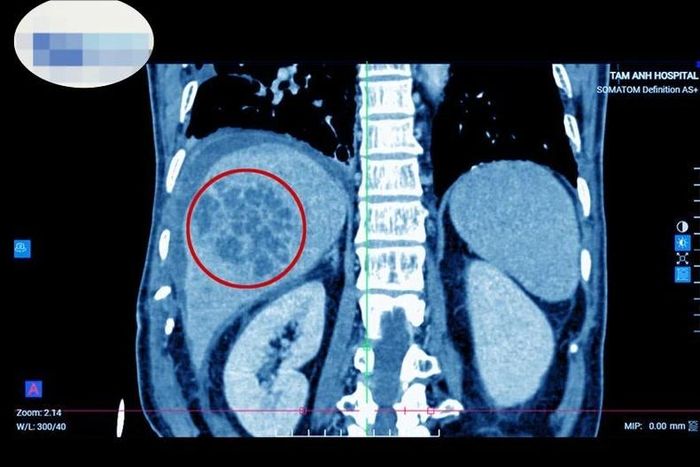

Bệnh nhân nam 71 tuổi, quê Nam Định đến khám tại Bệnh viện đa khoa Tâm Anh Hà Nội trong tình trạng sốt cao, đau bụng hạ sườn phải. Thạc sĩ, bác sĩ Phạm Khắc Khiêm, khoa Tiêu hóa cho biết, kết khám lâm sàng kết hợp cận lâm sàng như siêu âm, chụp cắt lớp vi tính phát hiện bệnh nhân có ổ áp xe ở gan phải, kích thước lớn khoảng 7*8cm. Quá trình hỏi bệnh được biết người bệnh có thói quen ăn gỏi cá nhiều năm nay. Xét nghiệm có kháng thể sán lá gan nhỏ, cấy mủ áp xe phát hiện vi khuẩn E.coli.

Hình ảnh ổ áp xe lớn (vùng khoanh đỏ), chiếm gần hết lá gan.